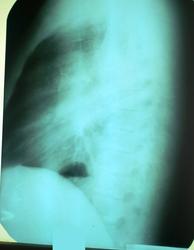

Мужчина, 40 лет. Жалуется на сильный кашель, задышку, сильную боль в левой половине грудной клетки. Ослабленный, худой, температура 37,1 - 37,3. Над левым легким, со слов терапевтов, не слышно ничего вообще. Меня терапевты, чесно признаюсь, запутали и торопили, хотя правильная мысль о диагнозе изначально была. Сделать томку не дали. Какие у кого будут мнения?

Справа повышенная воздушность легочной ткани. Слева легкое уменьшено в объеме, органы средостения смещены влево - вероятнее всего ателектаз (центральная форма рака?).

Надо исключать центральный рак. Газовый пузырь желудка поднят, скорее всего, из-за высокого стояния левого купола.

Плюсую за центральную обструкцию нижнедолевого бронха